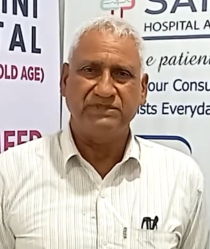

Meet Dr. S.N. Gupta – Senior Pulmonologist

30 Years of Excellence in Respiratory & Critical Care Critical Care

With over 30 years of clinical experience, Dr. S.N. Gupta is a highly respected pulmonologist dedicated to diagnosing, treating, and managing complex respiratory conditions. Known for a patient-first approach and evidence-based care, he has helped thousands of patients breathe easier and live healthier lives.

His expertise covers Respiratory Medicine, Critical Care, and Sleep Medicine, providing comprehensive care for both acute and chronic lung diseases.